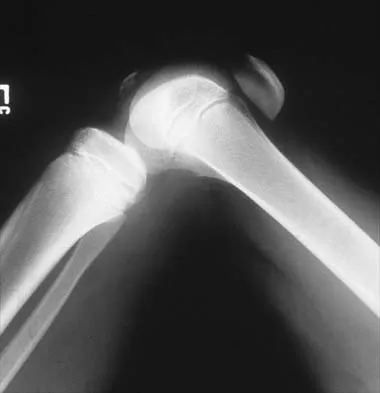

Figure 31 shows the AP and lateral radiographs of the elbow of a 56-year-old man with chronic polyarticular rheumatoid arthritis. His function continues to be limited by pain with activities of daily living. Examination shows that his total arc of motion is 110 degrees. Nonsurgical management has failed to provide relief. Treatment should now consist of

A semiconstrained prosthesis can provide excellent results in carefully selected patients. Because the radiographs show extensive joint destruction with loss of the capitellum and trochlea, a capitellocondylar total elbow (unconstrained) prosthesis is contraindicated. Elbow fusion is poorly accepted, and the radiographs show too much articular destruction for a radial head excision, synovectomy, or interposition arthroplasty to be effective. Ewald FC, Simmons ED Jr, Sullivan JA, et al: Capitellocondylar total elbow replacement in rheumatoid arthritis: Long-term results. J Bone Joint Surg Am 1993;75:498-507.